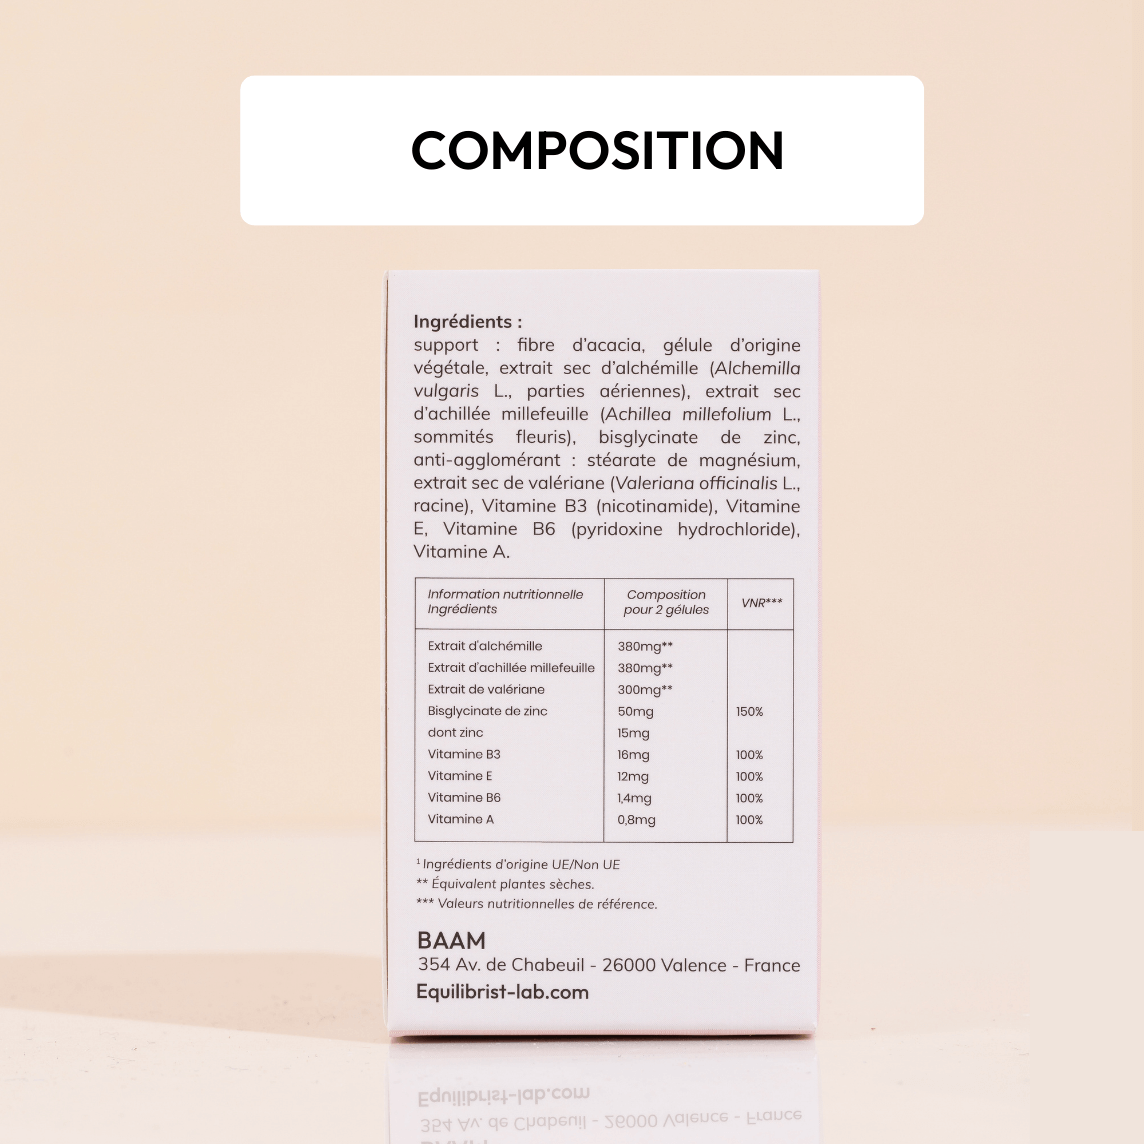

- Réequilibrage hormonal : l’Alchémille & l’Achillée millefeuille augmentent la production de progestérone

- Apport en vitamines & Zinc qui améliorent la régulation hormonale

- Soutien global, décontractant musculaire, antispasmodique & relaxant (Valériane)